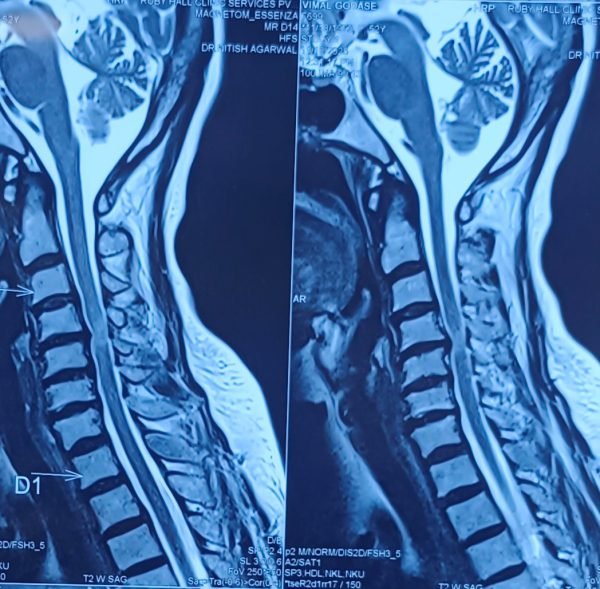

Posted on Nilesh KaduTrustindex verifies that the original source of the review is Google. I visited Dr. Nitish Agarwal for my severe back pain and shoulder issue. He checked my MRI very carefully and gave the perfect diagnosis. Yesterday, he performed the procedure (Root Block and Shoulder Injection), and it was completely painless. He is an expert and targeted the exact nerve point causing the trouble. Very helpful and humble doctor. Highly recommended for anyone with spine problems.Posted on Raju GorkhaTrustindex verifies that the original source of the review is Google. I was unable to make movement and suffered from right foot drop which is equal to halfway paralysis. Dr. Nitish Agarwal performed very fine microscopic surgery on L3, L4 & L5. After 90 days under his treatment I could go for a walk min. 6 kms a day, I have started my regular activities after 120 days. Thank you so much Dr. Nitish Agarwal sir.Posted on Pururaj GuravTrustindex verifies that the original source of the review is Google. I was suffering from severe back pain, and Dr. Nitish Agrawal has been extremely supportive throughout my treatment. He listened carefully, explained everything clearly, and guided me very well. His treatment has really helped me recover. He is one of the best spine specialists — highly recommended!Posted on Vinal AgrawalTrustindex verifies that the original source of the review is Google. I had consulted many doctors before Dr Nitish for my mother's spine issue,most recommended complex procedures and surgeries. Fortunately we found Dr Nitish and it has been life changing for my mother,she was in immense pain before the simple surgery he did. It's rare to find a surgeon who explains everything in detail and provides such exceptional care even after the surgery. I Would highly recommend him.Posted on Ajinkya MohadkarTrustindex verifies that the original source of the review is Google. My mother had sustained a fracture to her right hand wrist and we were worried about her recovery due to age factor. One of our family Doctor referred us to Dr. Nitish Agrawal and we visited Dr. Nitish Sir. Dr. Nitish sir ensured that my mother don't need a surgery and treated her by application of plaster (temporary and then cast-iron or Firm plaster) with certain orthopaedic treatment to hand and prescribed oral medication for ensuring recovery is faster without any surgery. Attaching the photo of xray which shows recovery of wrist bone which has rejoined and we are still continuing treatment to ensure my mother is fully recovered and is fit. Thank you Dr.Nitish Agrawal for your support.Posted on Samadhan LokhandeTrustindex verifies that the original source of the review is Google. Hi everyone, myself Samadhan. I was suffering from severe spine pain for a long time, and one of my friends suggested I visit Dr. Nitish Agarwal. Honestly, that was the best advice! Dr. Nitish listened to my problem very patiently, explained the cause in detail, and gave me the right treatment. I started feeling better within a short time. He is very polite, knowledgeable, and truly cares for his patients. I highly recommend Dr. Nitish Agarwal for anyone dealing with spine or back pain. Thank you, doctor, for your excellent treatment and support!Posted on POOJA JAGDALETrustindex verifies that the original source of the review is Google. Dr. Nitish Agrawal is an excellent spine specialist who patiently listens, explains the problem clearly, and provides the best treatment options.Posted on vipul pardeshiTrustindex verifies that the original source of the review is Google. Dr.Nitish sir is an incredible surgeon. I had excellent results from my recent spine surgery. The entire process, from consultation to recovery, was handled with professionalism and care. The outcome has been life-changing. I highly recommend Dr.Nitish agarwal to anyone in need of a spine surgeon.Posted on Deepak JadhavTrustindex verifies that the original source of the review is Google. A few months back I took treatment for my back pain from dr. Agarwal sir ...last 7-8 years i was suffering with low back pain,unbale to stand for more than 10 minutes..My low back hurts continuously, and also left leg pain was unbearable....i try every possible way of treatment from various suggestion...After several treatment...one of my relative suggested dr. Nitish Agarwal sirs name then I visited Dr. Nitish Agarwal sir in clinic. He suggested me x ray and MRI. On that basis he advise me caudal Block with root block with facet block for pain management. After block my pain goes with in a week. He advise me regular Physiotherapy at home. Now after regular exercise I am pain Free. Dr. Nitish Agarwal is a good doctor for any spine related problem.... Thank u dr. Agarwal Sir 🙏Posted on Kumar BTrustindex verifies that the original source of the review is Google. My wife had major infection in neck and lower back. She was bedridden. her legs and hands were weak. Then we admit her under Dr. Nitish Agarwal sir and did MRI. He explained that she is having major infection in cervical and lumbar spine. Due to infection her spinal cord is compressed so she was not able to walk. Then sir did operation for neck and removed infected tissue and spinal cord is freed and put a plate. Her lower back is treated with medicine only. She was given 2 months antibiotics by saline and 5 months oral antibiotics were given. He also advised regular exercise. After 15 days of surgery she started walking with support. Now after 1 year she is completely alright and walking like a normal person. She is regularly doing all her activities. Now she can also travel by 2 wheeler. Thank you to Dr. Nitish Agarwal sir for his expert work in spine. I recommend Dr. Nitish Agarwal for any spine related problem.